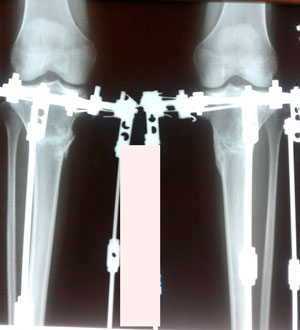

Дата операции - 12.08.2019.

Дата снятия аппаратов 05.2.2019.

Рентген пере снятием аппаратов!

IMG_7547-05-12-19-01-04.JPG

IMG_7546-05-12-19-01-04.JPG